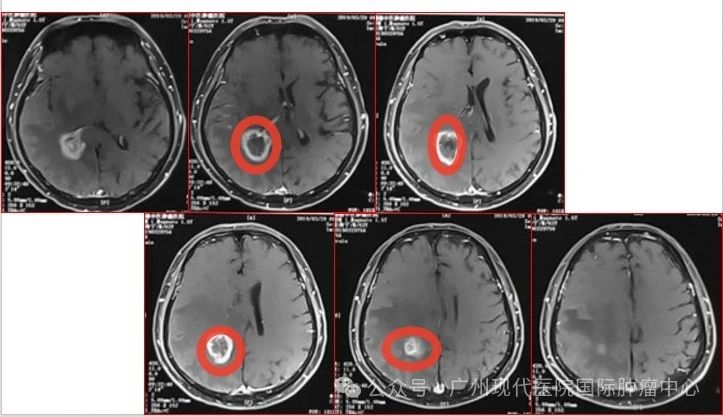

患者:63歲,男性

2013-11,體檢發(fā)現(xiàn)肺部腫瘤,

2015-11,頭顱MR檢查提示顱內(nèi)轉(zhuǎn)移

2018-11,顱內(nèi)腫瘤進(jìn)展,無(wú)法接受后續(xù)治療

2019-3,接受腦瘤粒子植入術(shù)

2019-7,顱內(nèi)腫瘤基本消失,正常生活至今

2019年7月,顱內(nèi)腫瘤已基本消失